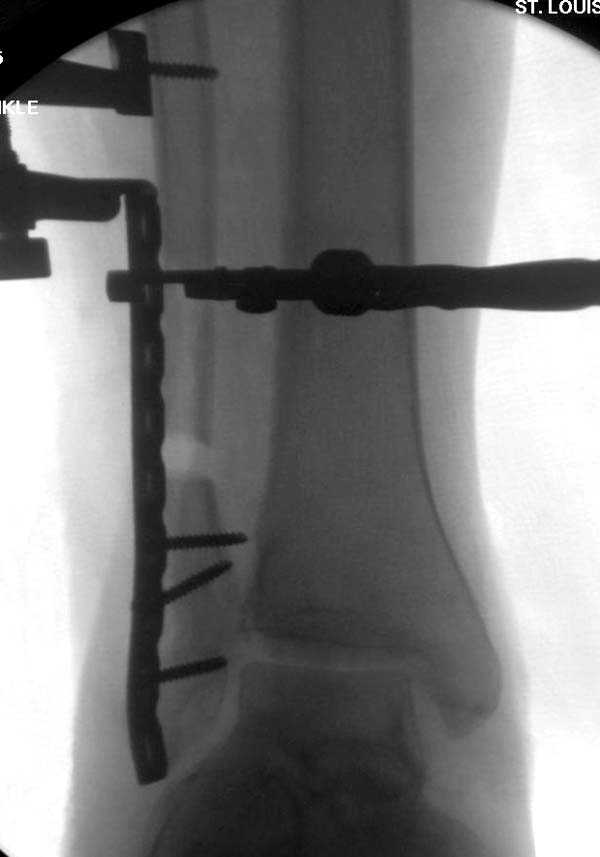

Здесь представлено решение похожей проблемы. Больной в течение года лечился консервативными мерами, и боли в голеностопе были основным показанием к операции.

Проведена обычная стандартная процедура по исправлению неудовлетворительного состояния голеностопного сустава, где кроме удлинения малоберцовой с применением compression tension device за проксимальный конец пластины, проведено замещение трикортикальным графтом из крыла, освобождение синдесмоза и медиальной щели от

фибротических масс с фиксацией.

Дополнительно у больного плоская стопа, во время операции провели небольшую скользящую остеотомию, надеемся, что поможет.